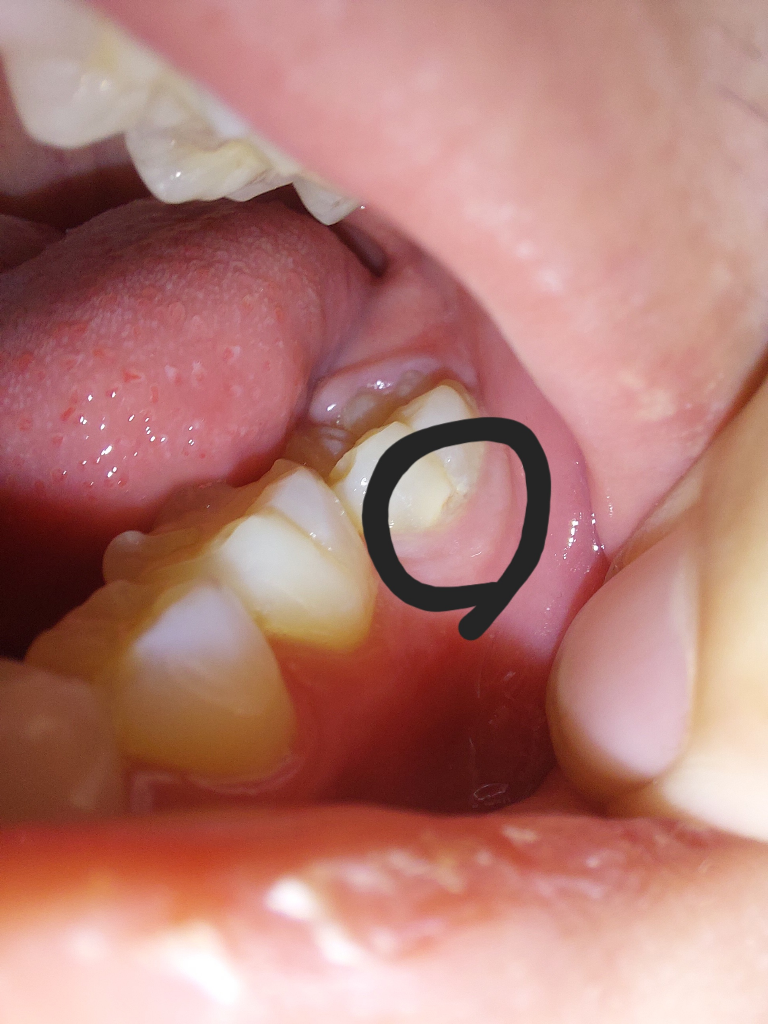

이빨이 깨졌는데 신경치료를 해야하나요?

이제 18살 됐고 이 이빨이 어금니 인지 사랑니 인지는 모르겠습니다. 왼쪽 아래 끝에 있는 이빨이고요 보니까 깨져있는거 같아요. 치과를 가보는게 나을까요? 가게되면 어느 정도의 치료를 받게 되나요? 또,이게 사랑니인지 어금니인지 사진상으로 구분 가능할까요?

잇몸도 부어있고 충치도 있습니다. 양치를 조금 더 신경써서 해주시는게 좋을 것 같고 아직 맹출이 덜 된 상태이고 충치치료를 하려면 잇몸밑까지 파야 해서 치료가 당장 안될 수도 있고 어쩌면 잇몸을 살짝 잘라내고 치료할 수도 있습니다. 자세한것은 치과가셔서 진료를 받아보셔야 할 것 같아요.

정확한건 치과에 가셔서 직접봐야 알수 잇을것같습니다. 사랑니는 아닌거 같고 마지막 치아 같습니다 저정도 깨진거라면 마취를 하고 충치치료를 해야되는데 아직 다 맹출된상태가 아니라 잇몸에 약간 뭍혀 잇어서 조금 기다렷다가 치료를 하셔야될수도 잇을것같습니다.

해당부위에는 충치가 진행이 되어 내부에서 부서진것으로 보입니다.

충치가 있는 부위는 치과에서 제거를 하고 치과용 재료로 충전을 해주는것이 좋습니다.

제 2대구치로 보여지며 떼우거나 씌우는 치료가 필요할수 있을것 같습니다.